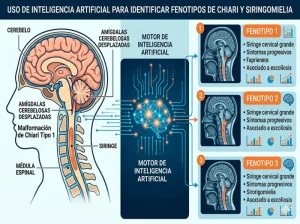

Uso de inteligencia artificial para identificar tres fenotipos de presentación de la malformación de Chiari tipo 1 y la siringomielia

Uso de inteligencia artificial para identificar tres fenotipos de presentación de la malformación de Chiari tipo 1 y la siringomielia En nuestra publicación reciente, identificamos 3 fenotipos de presentación de